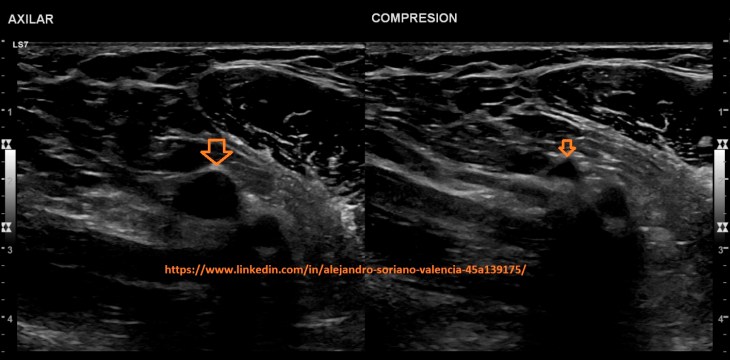

o Axilar.

Para esta vena el paciente tendrá que elevar y doblar el brazo para

colocar su mano detrás de la cabeza.

For this vein the patient will have to raise and bend the arm to place his hand behind the head.

5. Axilar transversal.

6. Axilar longitudinal. Estudio triplex.